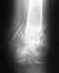

Рентгенограмму последнюю покажите.